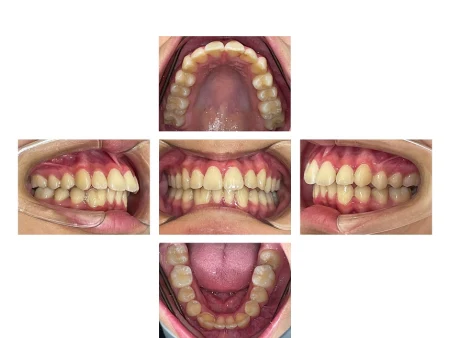

歯がきれいに並ぶよう、歯並びの幅をしっかり広げることを意識してマウスピースの設計を行い、治療を進めました。

歯がまっすぐ並び、口が閉じやすくなったことで歯ぐきの炎症も改善しました。

患者様にも「歯並びを気にせず過ごせるようになり、笑顔が増えた」と大変お喜びいただきました。

現在は歯並びの後戻りを予防するための「保定装置」をご使用いただき、定期的な経過観察をしています。